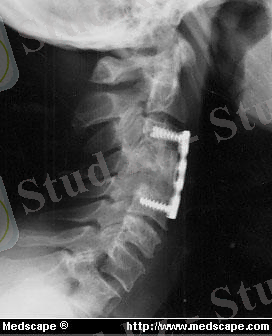

Мойын омыртқаларының сынығы мен шығуын емдеу.

Сынулар мен шығулардың бірсәтті қол репозициясы жұлынды зақымдау қаупі бар, сондықтан арнайы тәжірибелі дәрігер арқылы және рентген мен МРТ қорытындысынан кеін жасалады. Глиссон жіпшелерін тарту әдісі кең таралған , (рис. 16, а), бірақ бұл кезде 3 кг артық жүк қолданбайды. Сынықтар мен шығулар кезінде самай төмпектері арқылы қанқадан тарту қолданылады, бұл кезде ауыр жүктер қолданады, және сынық сипатына қарамастан жүк ауырлығын реттеп отыруға болады. (рис. 16, б, в), Рис . 16. мойын омыртқаларын тарту: а - Глиссон жіпшесі арқылы ; б, в - самай төмпектері арқылы

Репозиция мен рентген қорытындысынан кейін жүкті 3 - 4 кг азайтады. . 5 - 7 күннен кейін тартуды

торакокраниальды гипсті танғыш немесе ортезге ауыстырады.

(рис. 17) . Иммобилизация уақыты - 4ай

Рис . 17. омыртқаның мойын бөлімінің ішкі фиксациясы: а - торакокраниальды танғыш, б - тракционнды ортез; в -қатты ортез, г - қатқыл ортез.

Жоғары мойын омыртқаларының репозициясы мен фиксация HALO - aппараты арқылы жасалады. (рис. 18), сынық толық бітіскенге дейін қалтырады.

Рис. 18. HALO -аппарат

Консервативті репозиция әсер етпесе, немесе екіншілік ығысу, неврологиялық асқыну болғанда оперативті ем, дискэктомия, ығысқан омыртқаны орнына келтіру немес резекциясы жасалады. (рис. 19) .

Рис . 19. Сынықтышығудағы омыртқа денесінің бөлікті алып тасталуы. : а - мойын омыртқасының сынықты шығуы; б -операцияға дейінгі рентгенограмма; в, г - зақымданған омыртқаның денесінің бөлігін алу; д - дефектті трансплантатпен аутосүйек және жасанды кейджбен алмастыру. ; е -операциядан кейінгі рентгенограмма

Жақсы тұрақтылық пен ерте активизация үшін науқастарға арнайы пластина арқылы фиксация жасайды . рис. 20) .

Рис. 20. мойын омыртқаларның фиксациясы үшін Пластина CSLP: а, б - рентгенограммада; в - муляжда.